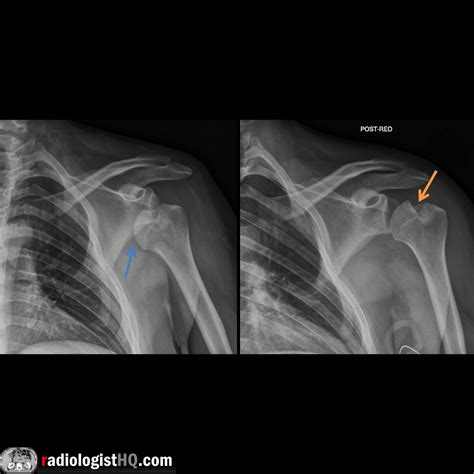

To accurately identify the extent of a Hills Sachs lesion, orthopedic specialists use various imaging techniques. A standard physical examination usually includes provocation tests to check for joint laxity, but the definitive diagnosis relies on high-quality medical imaging:

X-Ray (West Point View) Provides a specialized angle to visualize the bony defect of the humeral head.